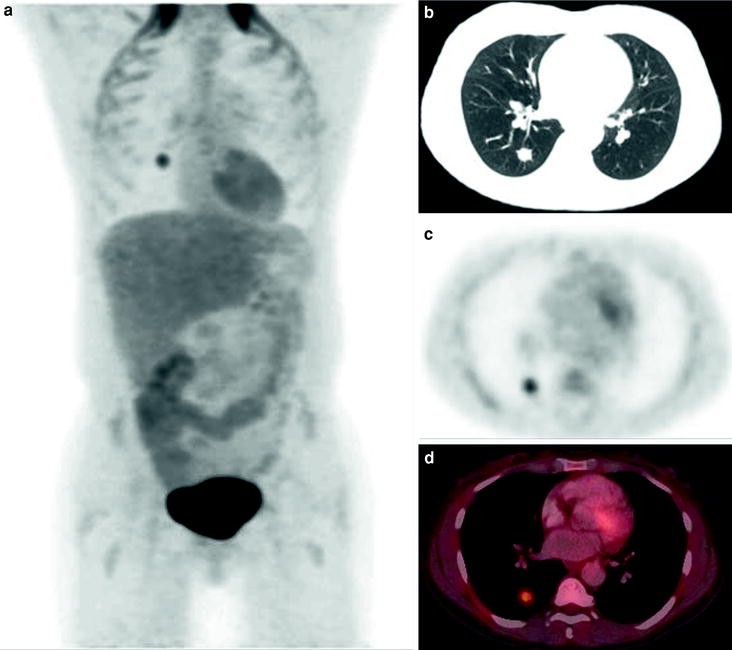

Miliary Mesothelioma A New Clinical And Radiological Presentation In Mesothelioma Patients With Prolonged Survival After Trimodality Therapy Sciencedirect

Miliary Mesothelioma A New Clinical And Radiological Presentation In Mesothelioma Patients With Prolonged Survival After Trimodality Therapy Sciencedirect from ars.els-cdn.com